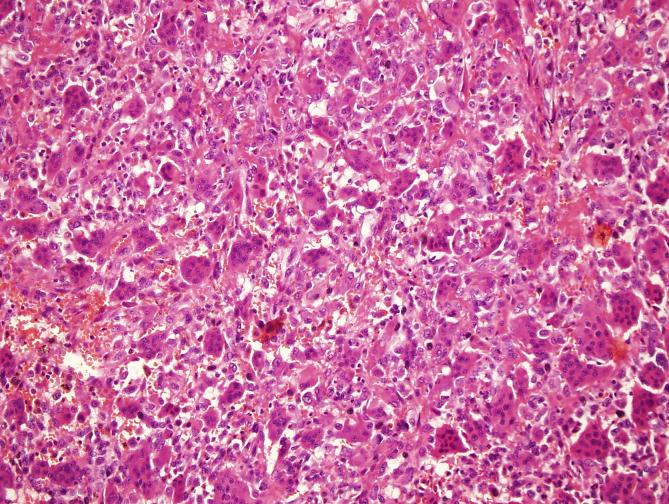

Tumors were localized most frequently at proximal tibia and distal femur, respectively. In 11 cases areas rich in fibrohistiocytic component and in 20 cases aneurysmal bone cyst like component were observed. In 2 cases both components were present. Twenty three cases recurred. In 1 case which was primarily located at calcaneus, tumor metastasized to lung 4 years later during follow-up.

GCT can be confused with other tumor or tumor-like lesions involving giant cells. Secondary changes such as fibrohistiocytic or aneurysmal bone cyst-like components and coagulation necrosis were frequently seen in conventional giant cell tumor of bone. For tumors having prominent fibrohistiocytic and/or aneurysmal bone cyst-like components, in order to detect characteristic areas representing GCT, additional sampling is essential. Although secondary histopathological changes do not appear to affect clinical outcome, these features are important in differential diagnosis. Approximately one fifth of GCT cases show recurrence and sacrum and foot bones were the most frequent sites for recurrence.

肿瘤最常分别位于胫骨近端和股骨远端。在11例中观察到富含纤维组织细胞成分的区域,20例中观察到动脉瘤样骨囊肿样成分。2例中两种成分均存在。23例复发。1例最初位于跟骨,随访4年后肿瘤转移至肺。

骨巨细胞瘤可能与其他涉及巨细胞的肿瘤或肿瘤样病变相混淆。在传统骨巨细胞瘤中,常见纤维组织细胞或动脉瘤样骨囊肿样成分以及凝固性坏死等继发性改变。对于具有显著纤维组织细胞和/或动脉瘤样骨囊肿样成分的肿瘤,为了检测代表骨巨细胞瘤的特征区域,额外取材至关重要。尽管继发性组织病理学改变似乎不影响临床结果,但这些特征在鉴别诊断中很重要。约五分之一的骨巨细胞瘤病例会复发,骶骨和足部骨骼是最常见的复发部位。